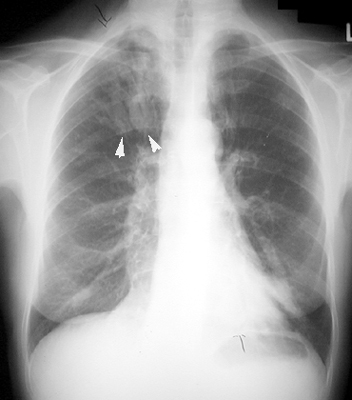

Bronchial Cast

"Gloved finger" appearance. Branching density. Inspissated mucus, distends bronchi giving such an appearance.